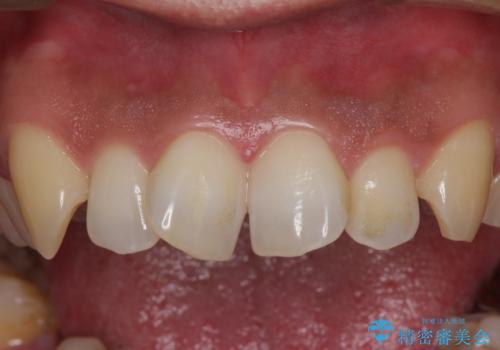

捻れた出っ歯の前歯 オールセラミッククラウンによる審美治療

- 前歯が捻れており出っ歯であることを気にして来院された患者様です。

虫歯がほとんどなく、前歯以外にも歯列に問題があったため、歯列矯正を第一選択として強く勧めました。

しかし、時間をかけることは避けたいという強い要望があったため、セラミッククラウンによる補綴治療を行うこととしました。